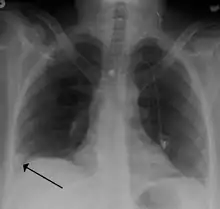

- Chest X-rays are often done on people with shortness of breath to help rule-out other causes, such as congestive heart failure and rib fracture. Chest X-rays in PE are rarely normal,[66] but usually lack signs that suggest the diagnosis of PE (for example, Westermark sign, Hampton's hump).